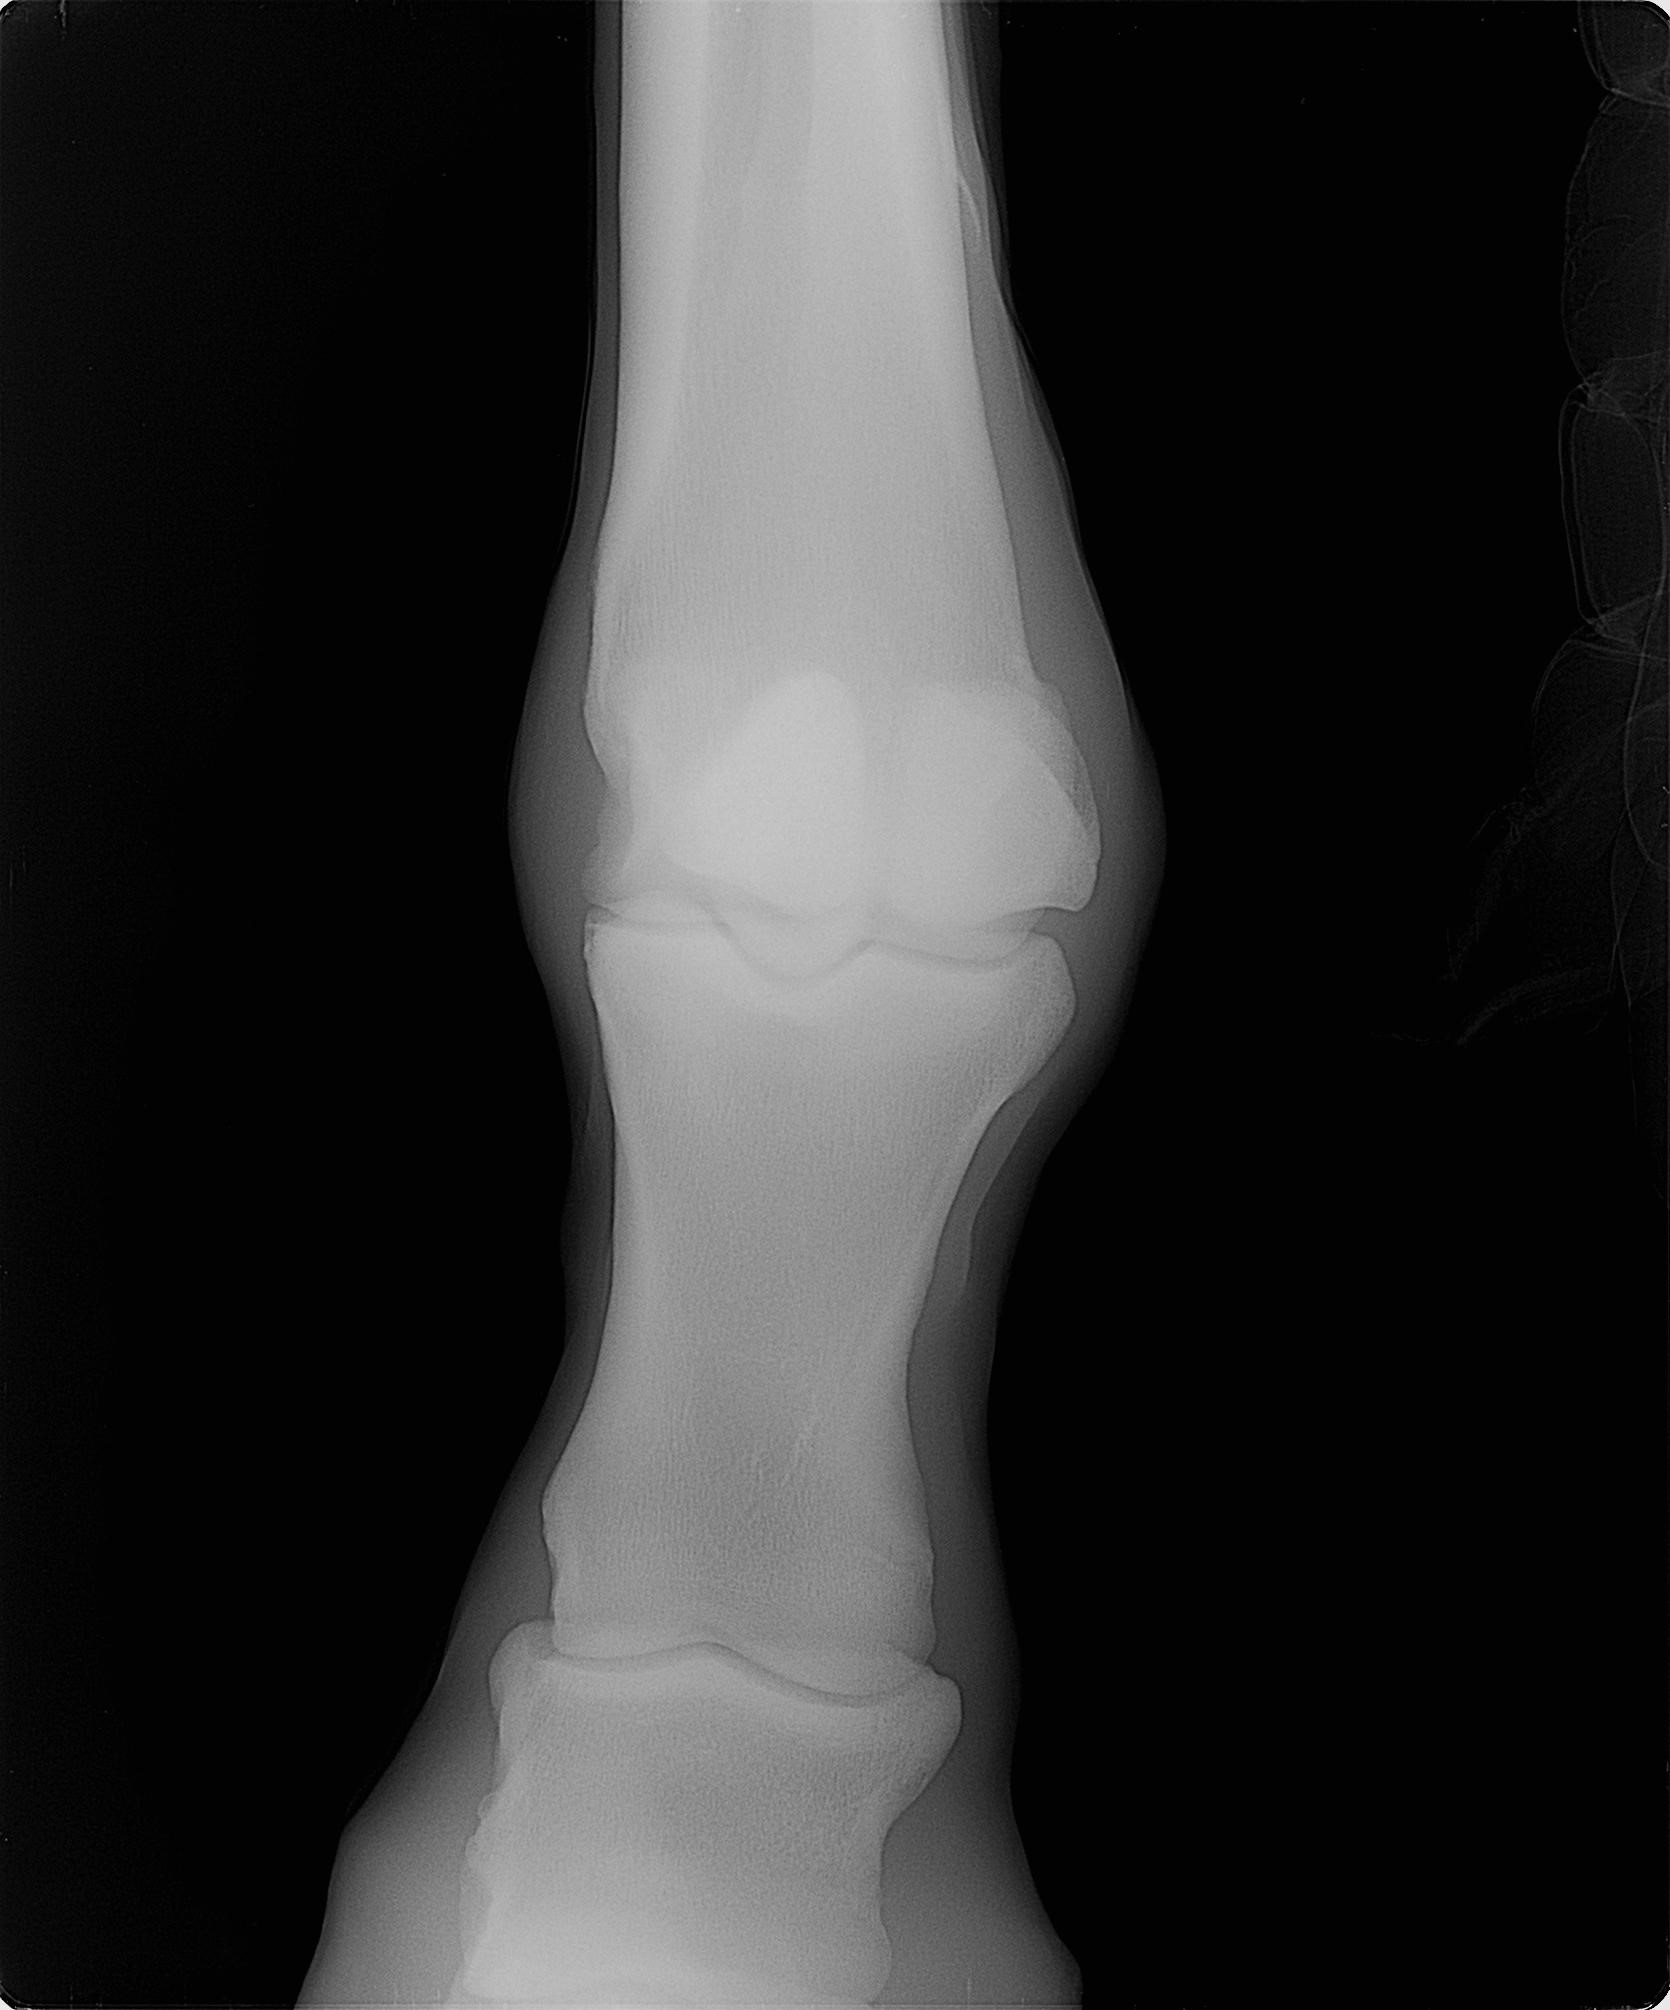

本馬は一時、坂路でハロン18秒ペースのキャンターまでペースアップしていたのですが、右トモが弱いこと、右前肢の蹄踵部を潰しやすいことが影響して順調に進めることができませんでした。2019年2月1日に右トモに跛行を呈したためレントゲン検査を実施したところ、右後肢第三中足骨遠位端亀裂骨折を発症していることが判明しました。現在は常歩レベルでは歩様に問題ないためウォーキングマシン運動を再開していますが、JRAでのデビューは厳しいと判断して今回のサラブレッドオークションへ出品することにいたしました。

2月1日に右トモが跛行したためレントゲンを撮ったところ、右後肢第三中足骨遠位端亀裂骨折を発症していました。レントゲン検査から1ヵ月ほど経過した現在は、速歩ではまだ跛行気味ですが常歩では問題ないため、現在はウォーキングマシンに入れて1時間歩かせているところです。右前肢の蹄踵部を潰しやすく、潰れると跛行してしまうため、エクイパックを充填して潰れないように処置しています。もともと右トモにも弱さがあって順調に進めることができておらず、ここから立ち上げてスムーズにいったとしても、デビューを迎えるのは夏以降になるでしょう。なお、右前の手根腱鞘部にはオステオコンドローマ(骨軟骨腫)があります。(EISHIN STABLE・渡辺場長)

※2019年2月1日に右後肢に跛行を呈したためレントゲン検査を実施したところ、右後肢第三中足骨遠位端亀裂骨折を発症していることが判明しました。

※右前の手根腱鞘部にオステオコンドローマ(骨軟骨腫)を発症しています。